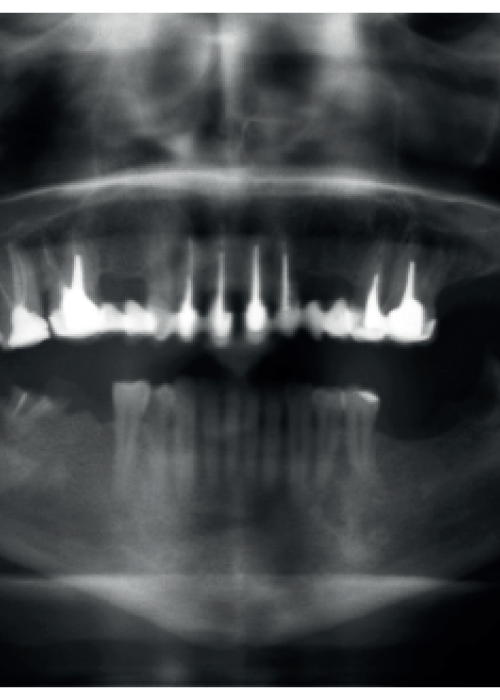

Enfoque conservador en paciente con múltiples lesiones periapicales radiolúcidas: Abordaje combinado endodóntico-quirúrgico